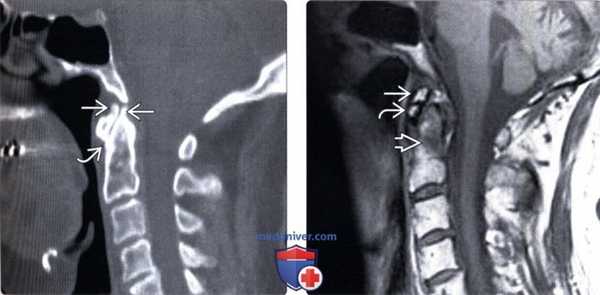

(Слева) На сагиттальной МРТ (Т2 ВИ) неотчетливо визуализируются тело С1 и остеофит. Определяется утолщение поперечной связки и гипертрофия синовиальной оболочки, что приводит к легкому объемному воздействию.

(Справа) На корональной реформатированной КТ в костном окне определяются признаки двухстороннего симметричного ОА боковых атланто-аксиальных суставов (нетипичная картина). В этом случае изменения, вероятно, обусловлены повышением нагрузки на суставы вследствие перелома зубовидного отростка без сращения. Определяются также признаки легкого ОА атланто-затылочных суставов.

(Слева) Т2-ВИ: тело С1 и остеофит визуализируются достаточно плохо, зато хорошо видна утолщенная поперечная связка и гипертрофированная синовиальная оболочка, несколько деформирующие дуральный мешок.

(Справа) КТ, фронтальный срез: картина двустороннего симметричного дегенеративного поражения латеральных атлантоаксиальных суставов, что встречается нечасто. В данном случае это связано скорее всего с избыточной подвижностью суставов на фоне несросшегося перелома зубовидного отростка. Атлантозатылочные суставы также с признаками умеренных дегенеративных изменений.